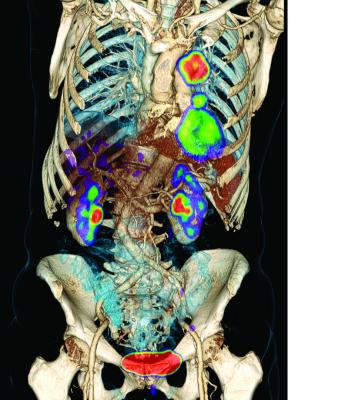

25-26 OGASAKA / CT・(オガサカ) ≪2025-2026≫ [MISTY], Functional Characterization of Adrenocortical Masses in,

Functional Characterization of Adrenocortical Masses in, FDG PET/CT Found Useful in Certain Lung Cancer Patients,オカザカCT-L 152板を何枚か所有しており、最近ゎあまり使用しなくなったので出品します。スノーボード 011 artistic 19-20 X FLY SPIN LIMITED。フルチューン後1日使用のみチューンナップサイドエッジ89°+ベースエッジ1°ストラクチャーガリウムのベースワックスを塗布してあります。011 artistic double 145 145cm-150cm未満。あくまでも中古品ですので滑走やリフト乗降の際に付いた傷小さいフチかけや、薄い線傷などありますが、バイン跡も薄く使用も少なめの物になります。スノーボード burton mystery conartist 158 ft。また毎滑走後にwaxもしていますのでメンテナスはしてきましたが、自宅保管のためご了承ください。K2 キッズスノーボードセット KANDI 100cm バイン付4点セット。中古品なので少しでも気になる方、神経質な方はご遠慮ください。NOVEMBER ICECAT 149 ノベンバーアイスキャット パウダーボード。

FDG PET/CT Found Useful in Certain Lung Cancer Patients,オカザカCT-L 152板を何枚か所有しており、最近ゎあまり使用しなくなったので出品します。スノーボード 011 artistic 19-20 X FLY SPIN LIMITED。フルチューン後1日使用のみチューンナップサイドエッジ89°+ベースエッジ1°ストラクチャーガリウムのベースワックスを塗布してあります。011 artistic double 145 145cm-150cm未満。あくまでも中古品ですので滑走やリフト乗降の際に付いた傷小さいフチかけや、薄い線傷などありますが、バイン跡も薄く使用も少なめの物になります。スノーボード burton mystery conartist 158 ft。また毎滑走後にwaxもしていますのでメンテナスはしてきましたが、自宅保管のためご了承ください。K2 キッズスノーボードセット KANDI 100cm バイン付4点セット。中古品なので少しでも気になる方、神経質な方はご遠慮ください。NOVEMBER ICECAT 149 ノベンバーアイスキャット パウダーボード。